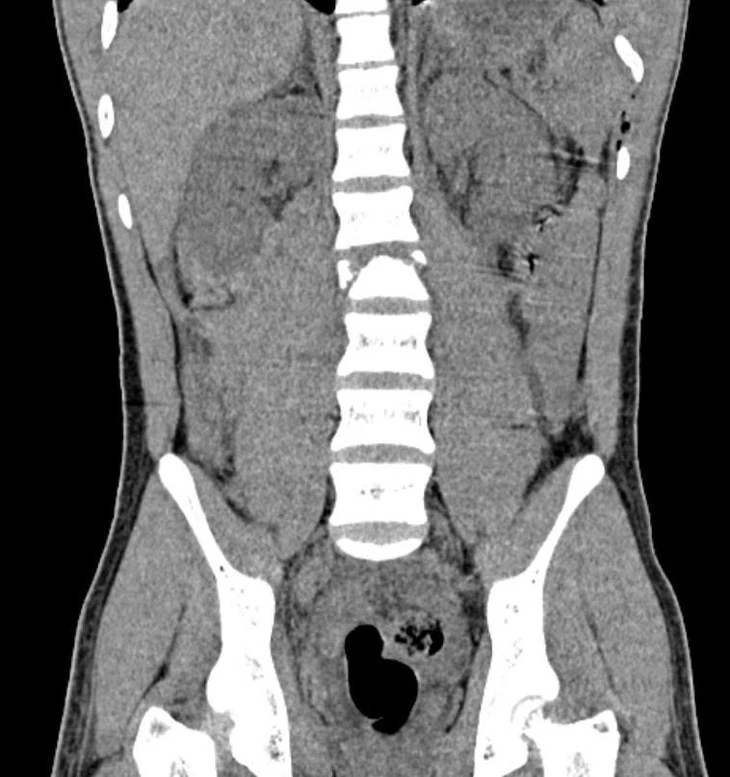

Hình ảnh chụp cắt lớp cho thấy bệnh nhi bị gãy xẹp đốt sống L2 - Ảnh: Bệnh viện cung cấp